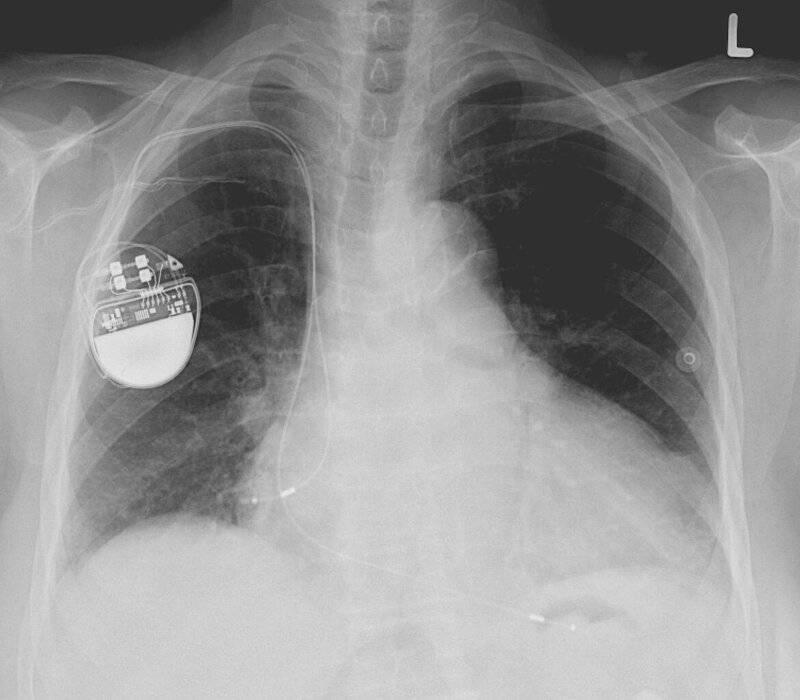

5. Pacemaker

10 Scientific Breakthroughs That Were Pure Accidents

“In tribute to Wilson Greatbatch, the pacemaker – a critical medical device – sits alongside technical drafts of its innovative design.” | Image from commons.wikimedia.org (Creative Commons Licensed)

Sometimes, a simple mistake can save millions of lives. In 1956, engineer Wilson Greatbatch was building a device to record heart sounds when he accidentally installed the wrong resistor in a circuit. Instead of recording, the circuit emitted rhythmic electrical pulses—remarkably similar to a human heartbeat.

Realizing the potential, Greatbatch refined the device into the world’s first implantable pacemaker, a breakthrough that allowed doctors to regulate irregular heart rhythms. This fortunate error revolutionized cardiac care and continues to help people around the globe. More info